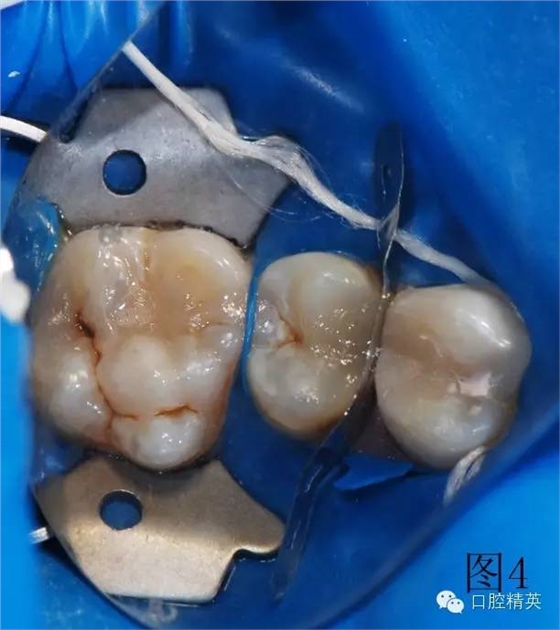

圖2、3為左上第一前磨牙充填結(jié)束,上橡皮障,充填另外兩顆牙。使用橡皮障,可以嚴密隔濕,防止樹脂受到污染,增加樹脂與牙齒之間的粘結(jié)力,延長充填物的使用壽命。

3顆牙充填完畢,卸下橡皮障夾和障布。